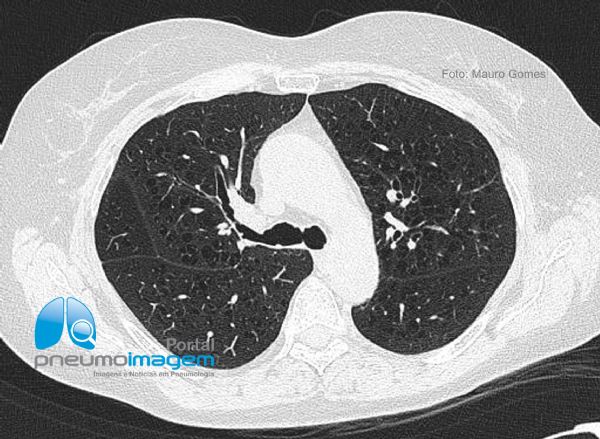

Centrilobular emphysema, or centroacinar emphysema, is the most common type of emphysema and is consequent to the dilation or destruction of respiratory bronchioles. In centrilobular emphysema there are multiple small thin-walled lucencies. When pneumonia occurs in a patient with emphysema, the resulting image can be confused with the pulmonary honeycombing observed in cases of pulmonary fibrosis, as in this slice of the upper regions.

After treatment and resolution of the infection, the areas of centrilobular emphysema can be seen and there is clearly no interstitial lung disease.